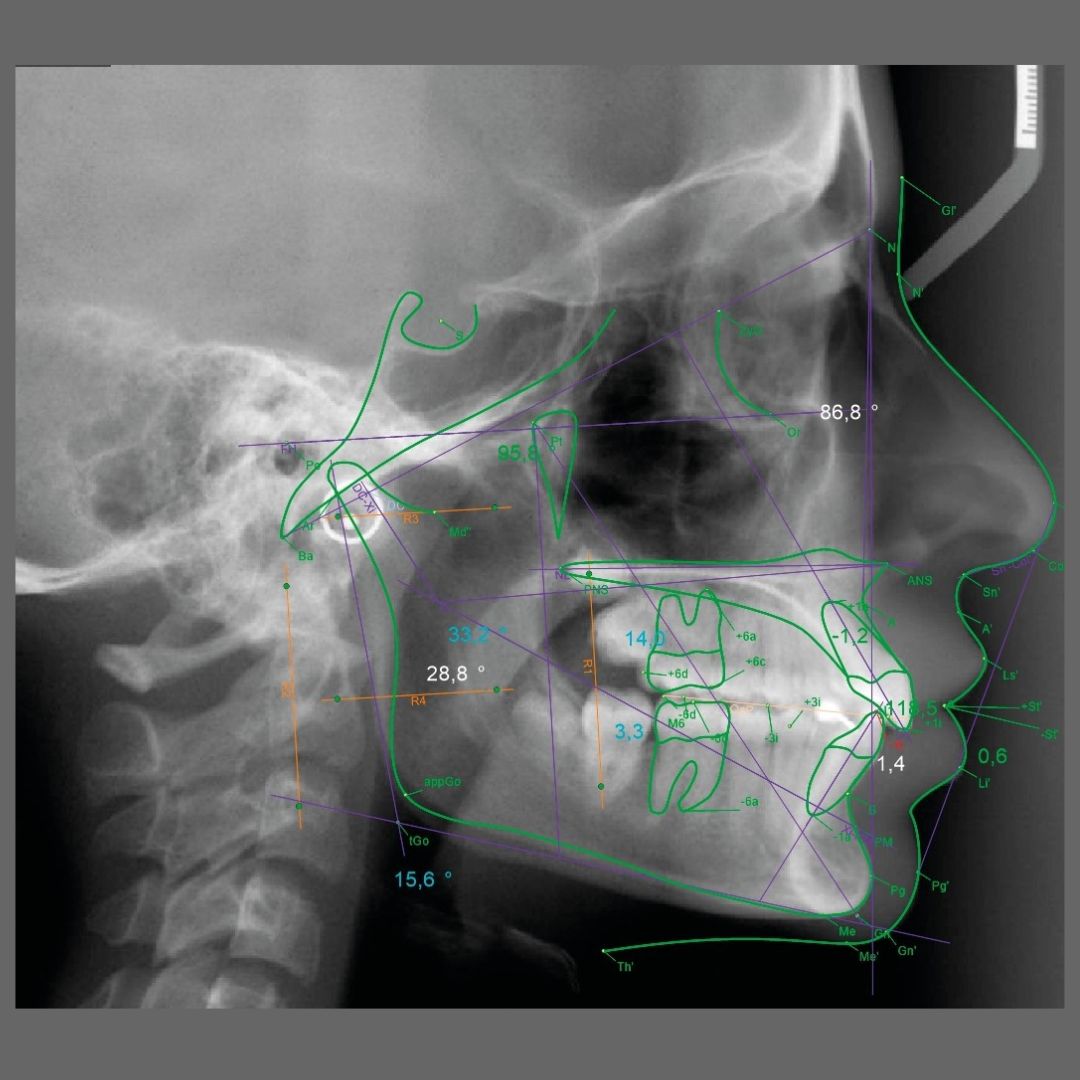

Estudios Adicionales

Trazado cefalométrico y fotografías clínicas con protocolos profesionales y alta precisión.